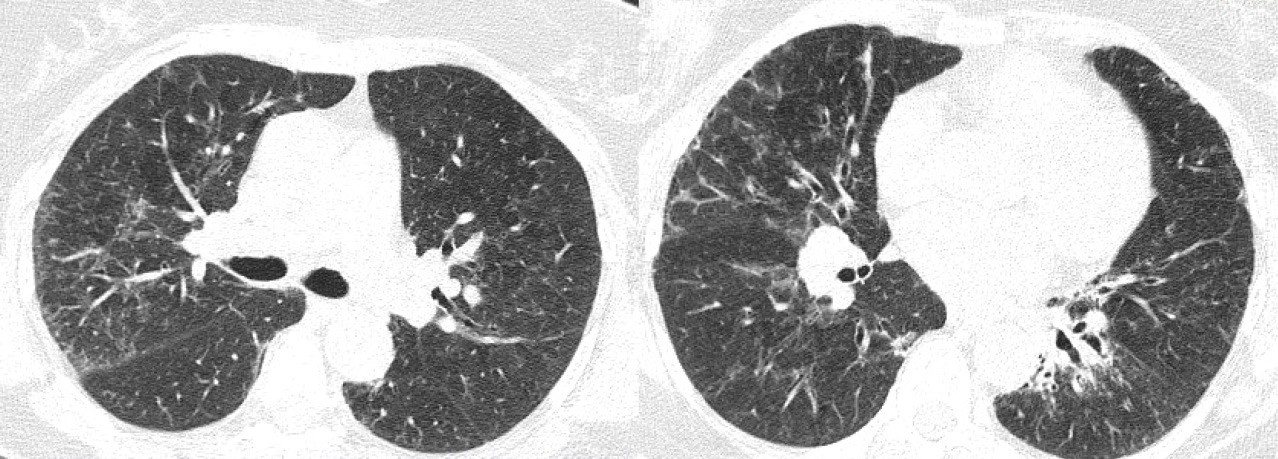

В мае 2020 г. пациентка заболела COVID-19, заболевание проявлялось главным образом в виде усиления одышки (по шкале mMRC 3 балла). Лечилась амбулаторно, принимала фавипиравир, антикоагулянты, левофлоксацин. В связи с появлением одышки при минимальной физической нагрузке и в покое, а также появлением отеков нижних конечностей в сентябре 2020 г. были рекомендованы формотерол/будесонид 12/400 мкг, тиотропия бромид 18 мкг, фуросемид. Выполнена КТ ОГК, при которой описана отрицательная динамика (рис. 2). SatO2 92%. От предложенной госпитализации пациентка отказалась. К врачу до марта 2021 г. не обращалась, не обследовалась, продолжала принимать рекомендованную ингаляционную терапию.

Рис. 2. Компьютерная томография органов грудной клетки: аксиальные срезы. Полиморфные ретикулярные изменения на фоне зон «матового стекла». Расширение бронхов по типу бронхиолоэктазов и бронхоэктазов. Признаки «сотового легкого» в заднебазальных отделах